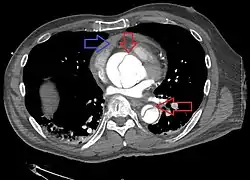

Computed tomography

Computed tomography angiography is a fast, noninvasive test that gives an accurate three-dimensional view of the aorta. These images are produced by taking rapid, thin-cut slices of the chest and abdomen, and combining them in the computer to create cross-sectional slices. To delineate the aorta to the accuracy necessary to make the proper diagnosis, an iodinated contrast material is injected into a peripheral vein. Contrast is injected and the scan performed using a bolus tracking method. This type of scan is timed to an injection to capture the contrast as it enters the aorta. The scan then follows the contrast as it flows through the vessel. It has a sensitivity of 96 to 100% and a specificity of 96 to 100%. Disadvantages include the need for iodinated contrast material and the inability to diagnose the site of the intimal tear.

Aortic dissection

Chest CT with descending (type B Stanford) aortic dissection (red circle)